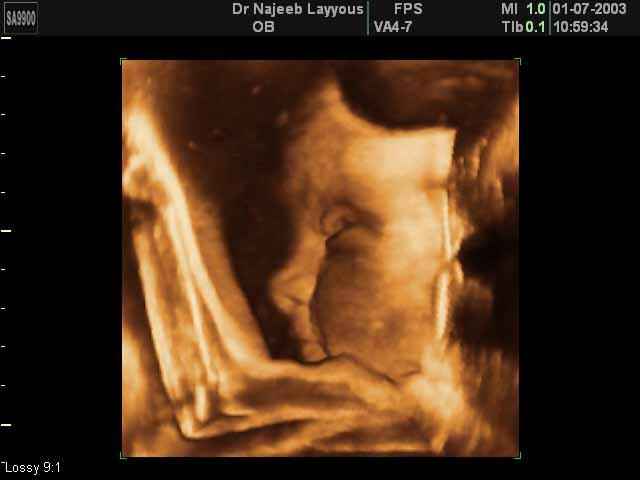

صور جانبية لرأس الجنين بجهاز الالتراساوند ثلاثي الأبعاد | الدكتور نجيب ليوس